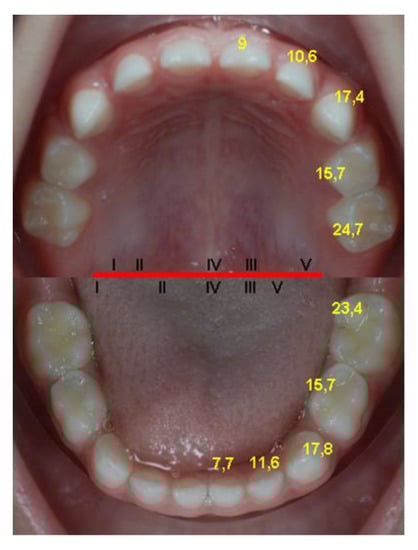

Figure 4.

Reference values of timing (months) and sequence of primary teeth eruption (tooth numbers of the upper and lower jaw quadrant, in relationship to the red line) in our sample.

The eruption sequence is the same in all the studies, with very few exceptions, among which we mention the study conducted on the A group by E. Bratu, where the primary central maxillary incisors erupt before the mandibular ones, the rest of the sequence being preserved. The primary lateral maxillary incisors erupt before the mandibular incisors in all cases, with the exception of the standards described by Stöckli and those described by Peltomäki, where the eruption ages are not differentiated between them. Proffit, however, differentiates between them. The primary canines and first primary molars of the maxilla erupt at about the same time as the mandibular ones, and the primary mandibular secondary molars erupt before the maxillary ones (Figure 4). Determining almost the same sequence of eruption proves that this is under a strong genetic control, the environmental factors being able to influence to a greater extent the age of eruption of different groups of teeth or individual dental units [38,39,41].